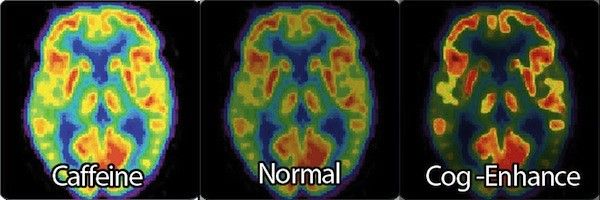

In particolare alcuni player di Counter Strike hanno dichiarato di giocare sotto l'effetto di questa anfetamina studiata per aumentare di molto i livelli di concentrazione dell uomo, viene infatti solitamente utilizzata per malattie caratterizzata da deficienza di attenzione.

Queste droghe inoltre sono state indicate come PED (Performance Enhancing Drugs), droghe che di fondo migliorano le performance, proprio sulle PED l'ESL ha dichiarato